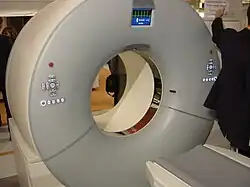

Jeder CT-Scanner besitzt einen kurzen Ringtunnel, auch Gantry genannt, sowie einen elektromotorisch beweglichen Tisch, auf dem der Patient bzw. das Untersuchungsobjekt liegt. Im Rahmen der Untersuchung wird das zu untersuchende Körperteil oder Objekt parallel zum Aufnahmeprozess durch diesen Tunnel gefahren. Für die Erzeugung der Hochspannung, Berechnung der Daten und Steuerung des Gerätes sind meist noch ein oder mehrere Schaltschränke vorhanden, die jedoch variabel platzierbar sind. Sie können sich im Untersuchungsraum, im Bedienraum oder in einem getrennten Raum befinden. Außerhalb des Untersuchungsraumes befindet sich die Bedienkonsole, mit der das Personal den Ablauf der Untersuchung steuert.

Typischer CT-Scanner: Im Bild vorne, rechts: Gantry und Patiententisch. links neben Gantry: die Kontrastmittelpumpe zur Verabreichung eines Kontrastmittels. In rechter Raumecke eine Stromversorgungseinheit mit Transformatoren, rechts daneben ein Geräteschrank.

Typischer CT-Scanner: Im Bild vorne, rechts: Gantry und Patiententisch. links neben Gantry: die Kontrastmittelpumpe zur Verabreichung eines Kontrastmittels. In rechter Raumecke eine Stromversorgungseinheit mit Transformatoren, rechts daneben ein Geräteschrank. -